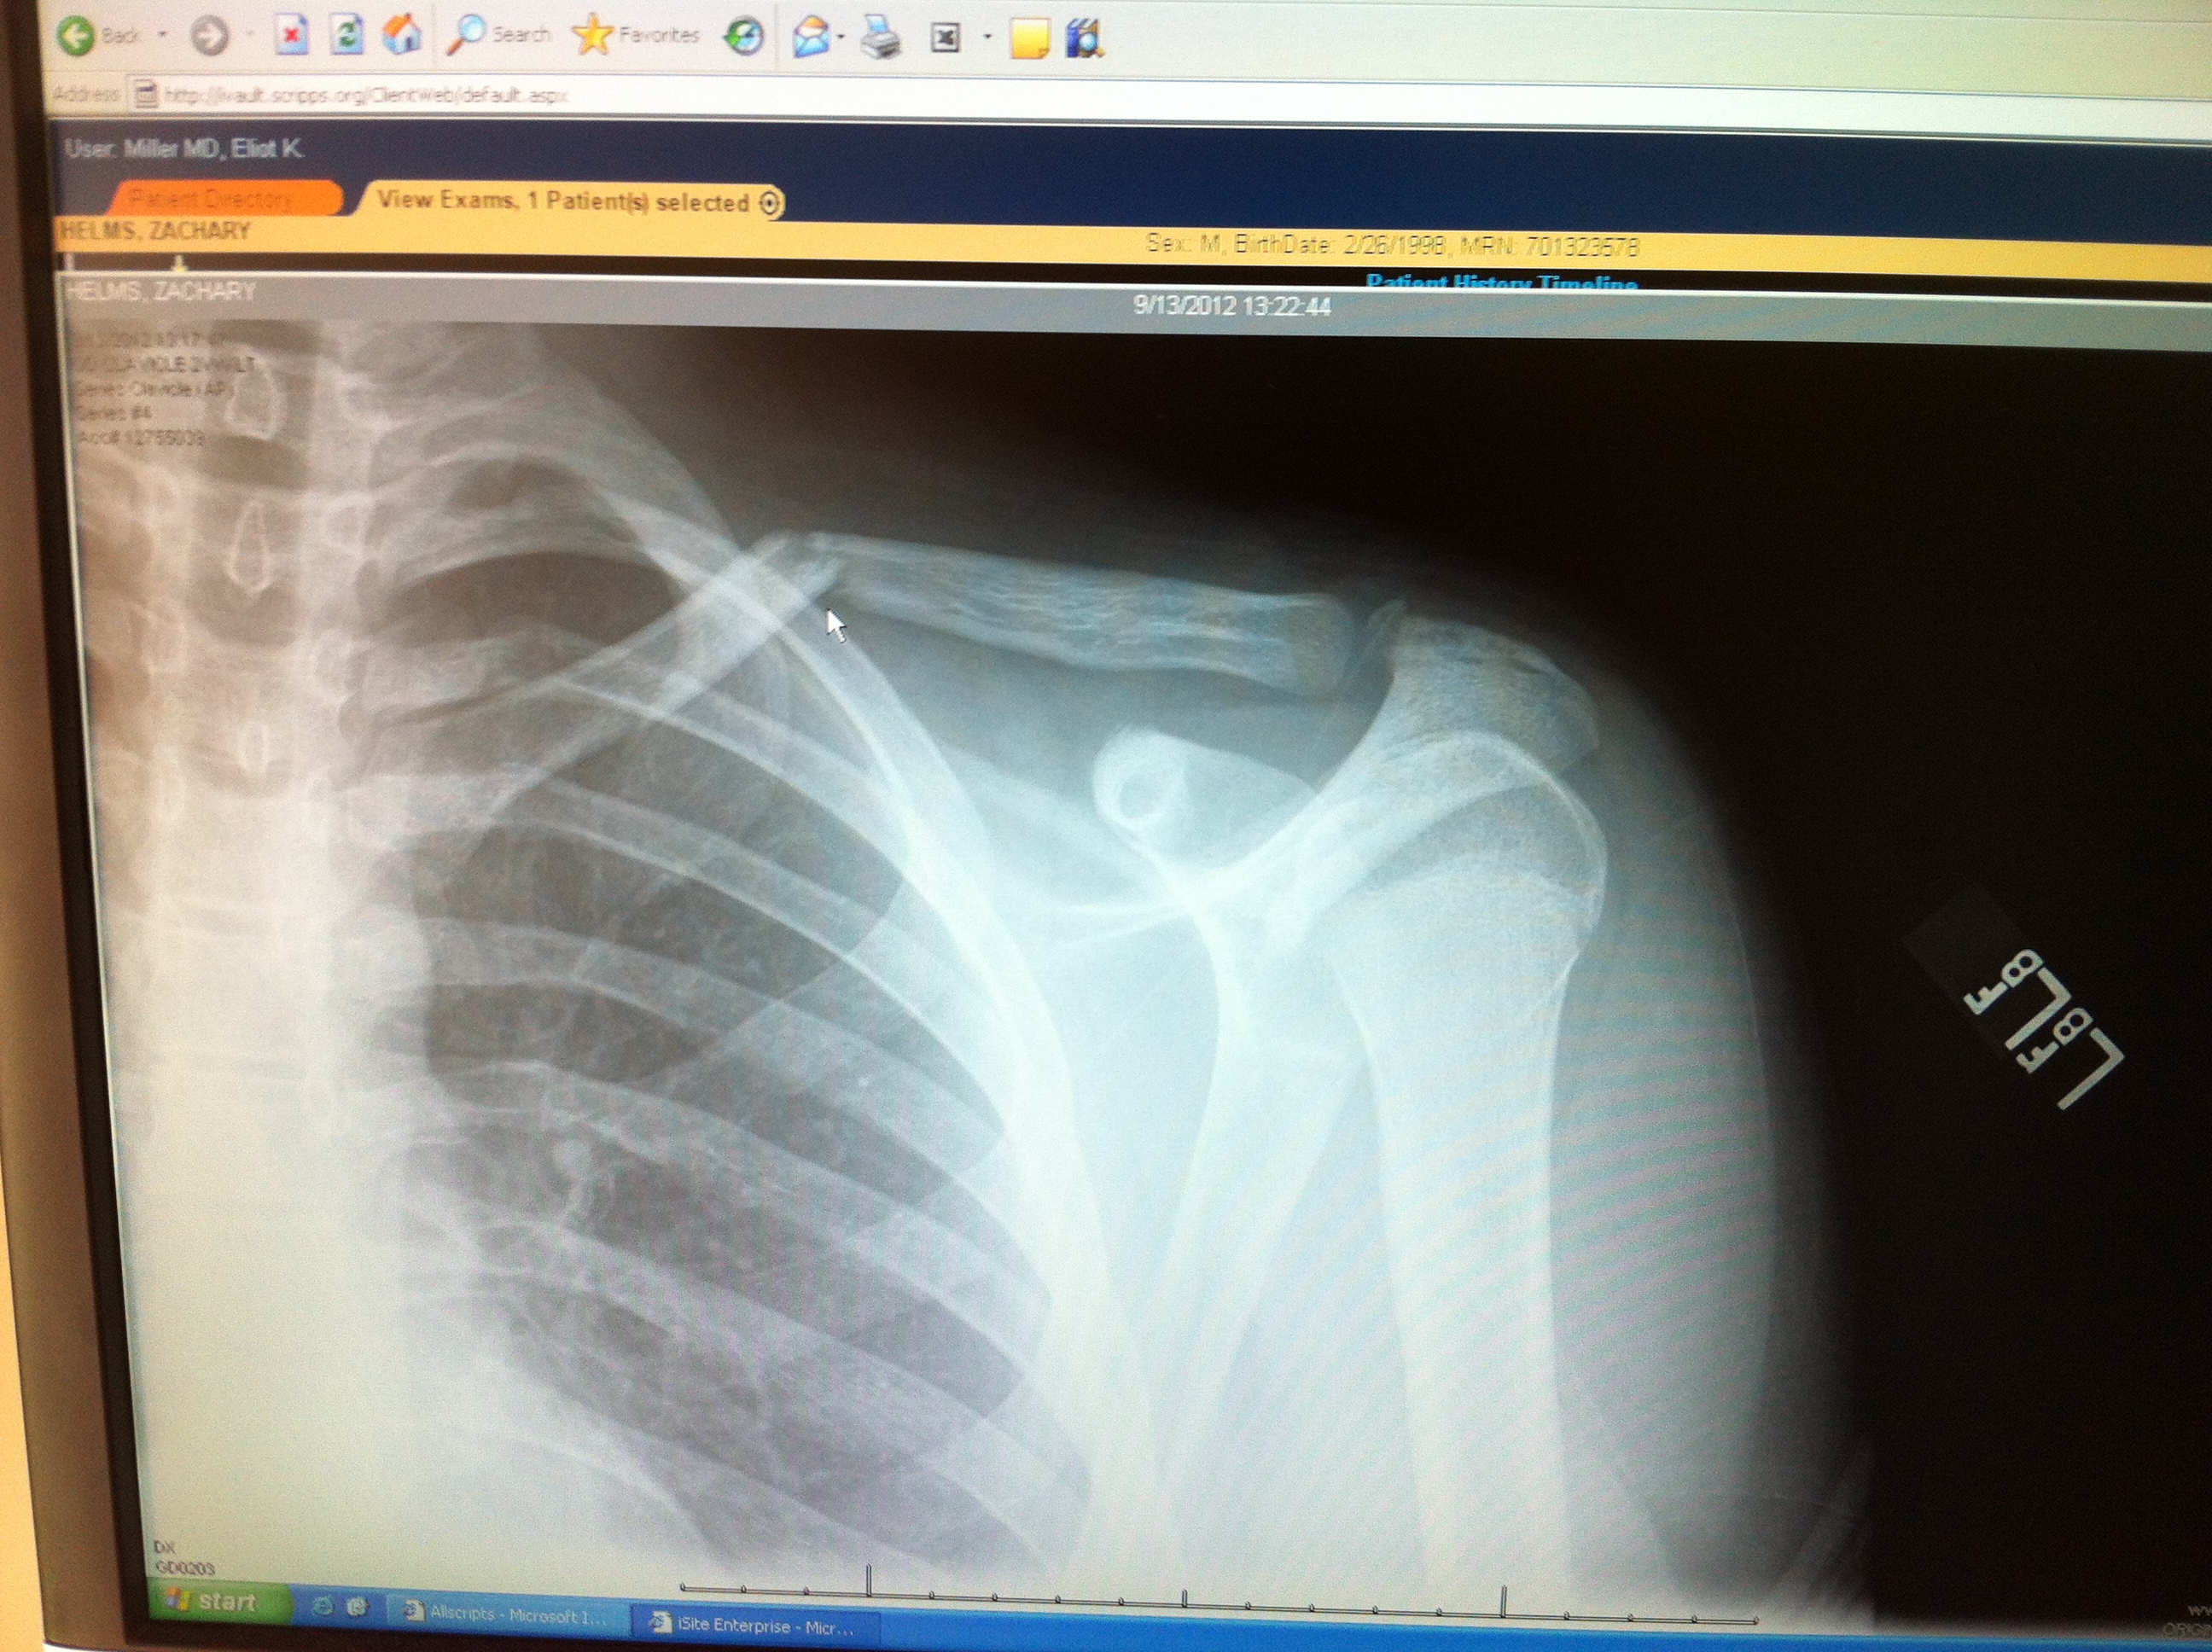

This, my friends, is what a fractured collar bone looks like.

He has a sling now and orders to take ibuprofen and a prescription for something stronger. He will be out of P.E. for six weeks and he’s so sad that he can’t play his guitar, either.